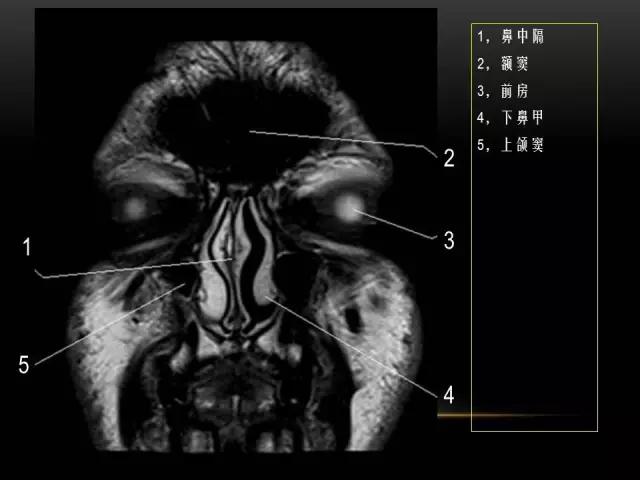

下文是在MRI下眼部及鼻窦的冠状位解剖图谱。